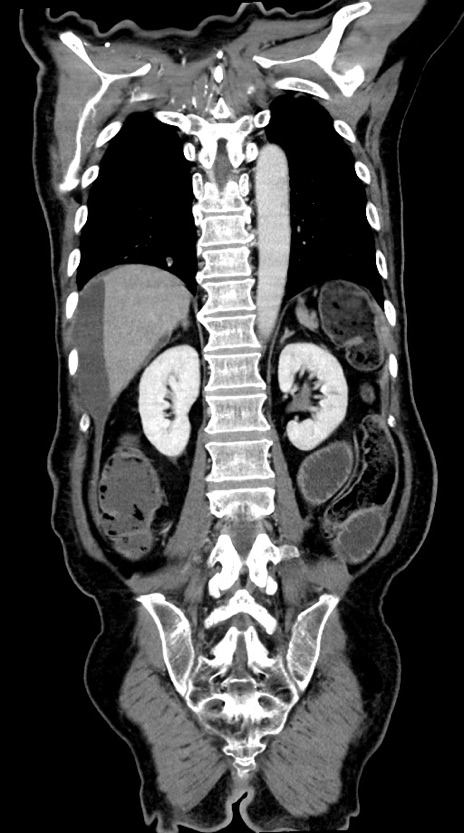

症例28(冠状断像)

【症例】60歳代男性

【主訴】嘔吐

【現病歴】胃癌にて胃全摘後。食思不振が悪化し、夜中に嘔吐することがある。

【既往歴】胃癌、胃全摘、脾摘、胆摘後

【データ】WBC 5900、CRP 10.56